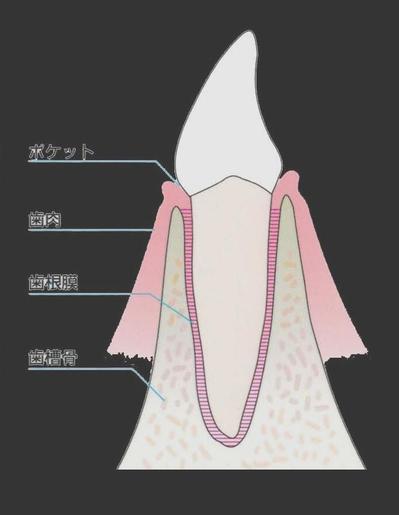

歯は歯槽骨という骨に支えられています。

あなたの歯がまだしっかりとしてグラグラともしていないのは、

この歯を支えている骨がしっかりしているからなのです。

歯は歯槽骨という骨に支えられています。

あなたの歯がまだしっかりとしてグラグラともしていないのは、

この歯を支えている骨がしっかりしているからなのです。

歯を支えているのは骨なのです。

下の図でいえば

大根が歯、

黄土色部分が、骨です。

大根も顔の頭が見えているのは3分の1程度で

残りに3分の2は骨に埋まっています。

骨が溶けるとはどういうことでしょうか。

よく分からないですよね。

歯の周りの骨が溶けるということです。

骨が溶けたら歯は支えられませんから歯が抜けます。